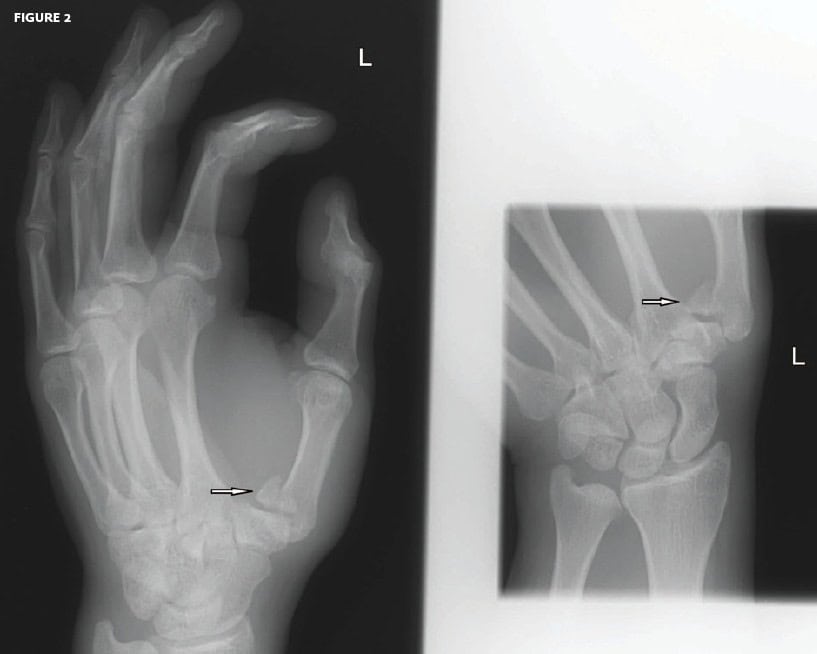

This patient presented with a jammed thumb.